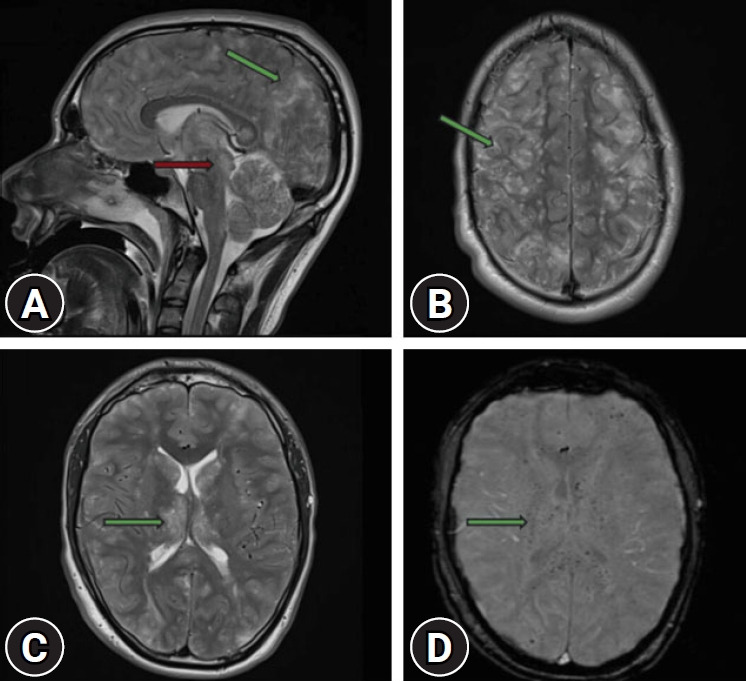

脂肪栓塞综合征(FES)是一种罕见但严重的并发症,最常与创伤有关,特别是长骨骨折。然而,有症状的FES仍然是一个重大的诊断和治疗挑战。我们报告了一个20岁的男子,在摩托车事故中持续多处长骨骨折后,最初表现稳定,经历了快速和致命的FES进展。本病例强调了即使在以前健康的年轻人中,FES的病程也是不可预测的,并强调了早期识别和干预的迫切需要。它还强调了确定可能预测严重后果和死亡率的风险因素的重要性。

Fat embolism syndrome (FES) is a rare but serious complication most commonly associated with trauma, particularly long bone fractures. However, symptomatic FES remains a significant diagnostic and therapeutic challenge. We present the case of a 20-year-old man who, after sustaining multiple long bone fractures in a motorcycle accident and initially appearing stable, experienced a rapid and fatal progression of FES. This case underscores the unpredictable course of FES even in young, previously healthy individuals and highlights the critical need for early recognition and intervention. It also emphasizes the importance of identifying risk factors that may predict severe outcomes and mortality.